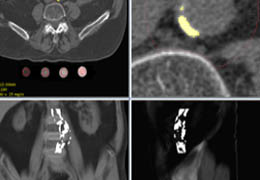

View X-Ray CT & MRI Scans Fast and Easily

Designed for surgeons, Pro Surgical 3D makes it easy to view patient scans quickly. Pro Surgical 3D facilitates the optimal 3D treatment and assessment workflows based on X-ray CT and MRI scans – and best of all, it’s FREE!

Traditional multi-planar slicing

High-quality and fast 3D reconstruction and 3D rendering

Multi-planar slicing.

Oblique slicing.